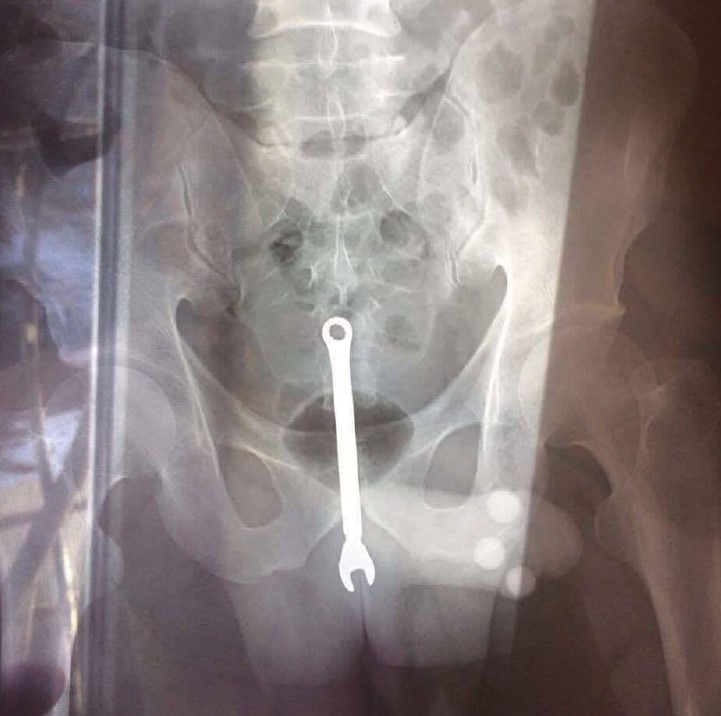

Ключ пожалуйста, ДА НЕ ТУДА!

Обычный московский автослесарь дважды за новогодние праздники оказался в больнице. У него в заднице застрял гаечный ключ. Дважды.

Что именно пытался развинтить Михаил – неизвестно, врачам он заявил, что это была производственная травма, он, мол, на ключ случайно упал. Металлическое орудие благополучно извлекли, решив не задавать уточняющих вопросов. Инструмент Миша попросил завернуть с собой, – всё-таки работа в сервисе на целый день встала.

Услышав столь пронзительную историю, врачи на всякий случай поинтересовались, стоит ли им извлекать инородное тело, ставшее Михаилу уже родным. Потом в ходе недолгой операции ключ всё же достали, мужчина поблагодарил врачей и забрал инструмент с собой. С тех пор прошло около недели, пока Миша не возвращался.

Ключ на триста.